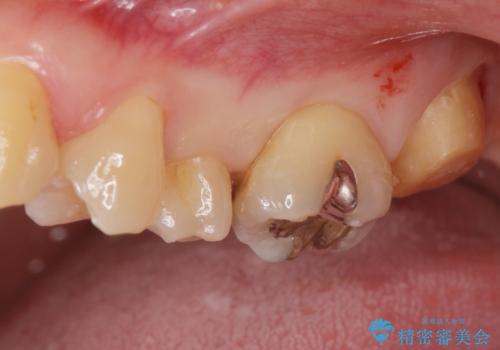

- 奥歯の歯が黒いとの事で来院された患者様です。

頬側の歯の面も粗造になっていたので、インレーではなくジルコニアクラウンでの治療となりました。